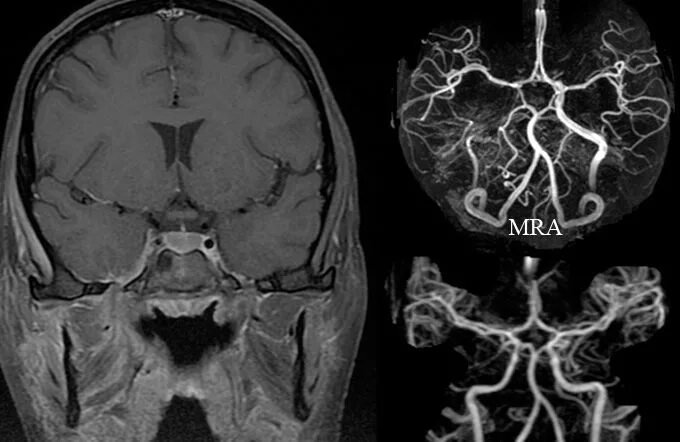

Тромбоз кавернозных